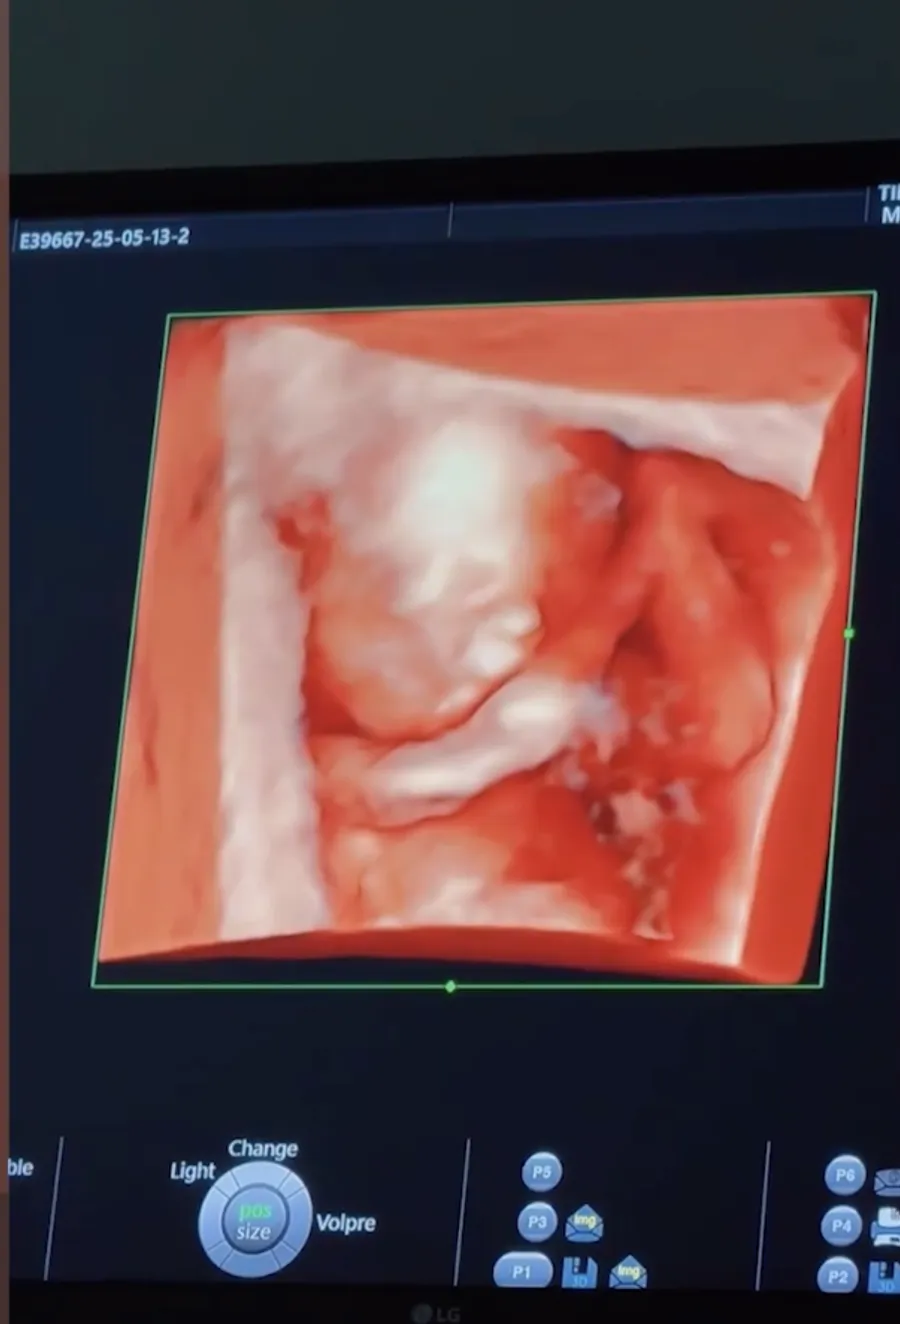

Vestea unei noi sarcini vine într-un moment în care Laura și Bogdan par să se afle într-o etapă matură și stabilă a relației lor. Deși nu au oferit multe detalii privind sexul copilului sau perioada estimată a nașterii, imaginile postate pe rețelele de socializare reflectă un climat de bucurie și anticipare. Clipul publicat de cei doi îi include și pe Matti, fiul Laurei, care se arată încântat de ideea de a deveni frate mai mare. Micuțul a fost surprins într-un gest afectuos, sărutând burtica mamei sale.

„A fost o sarcină planificată, nu a fost o întâmplare, în sensul în care ne doream să avem un copil și am lăsat lucrurile în voia lui Dumnezeu. Și iată! Primul trimestru a fost mai greu că m-am simțit destul de rău, spre deosebire de prima sarcină. Matti a fost extrem de fericit, este foarte grijuliu, deja se gândește cum să-și transforme camera sa fie baby friendly”, a spus Laura Mușuroaea pentru viva.ro.